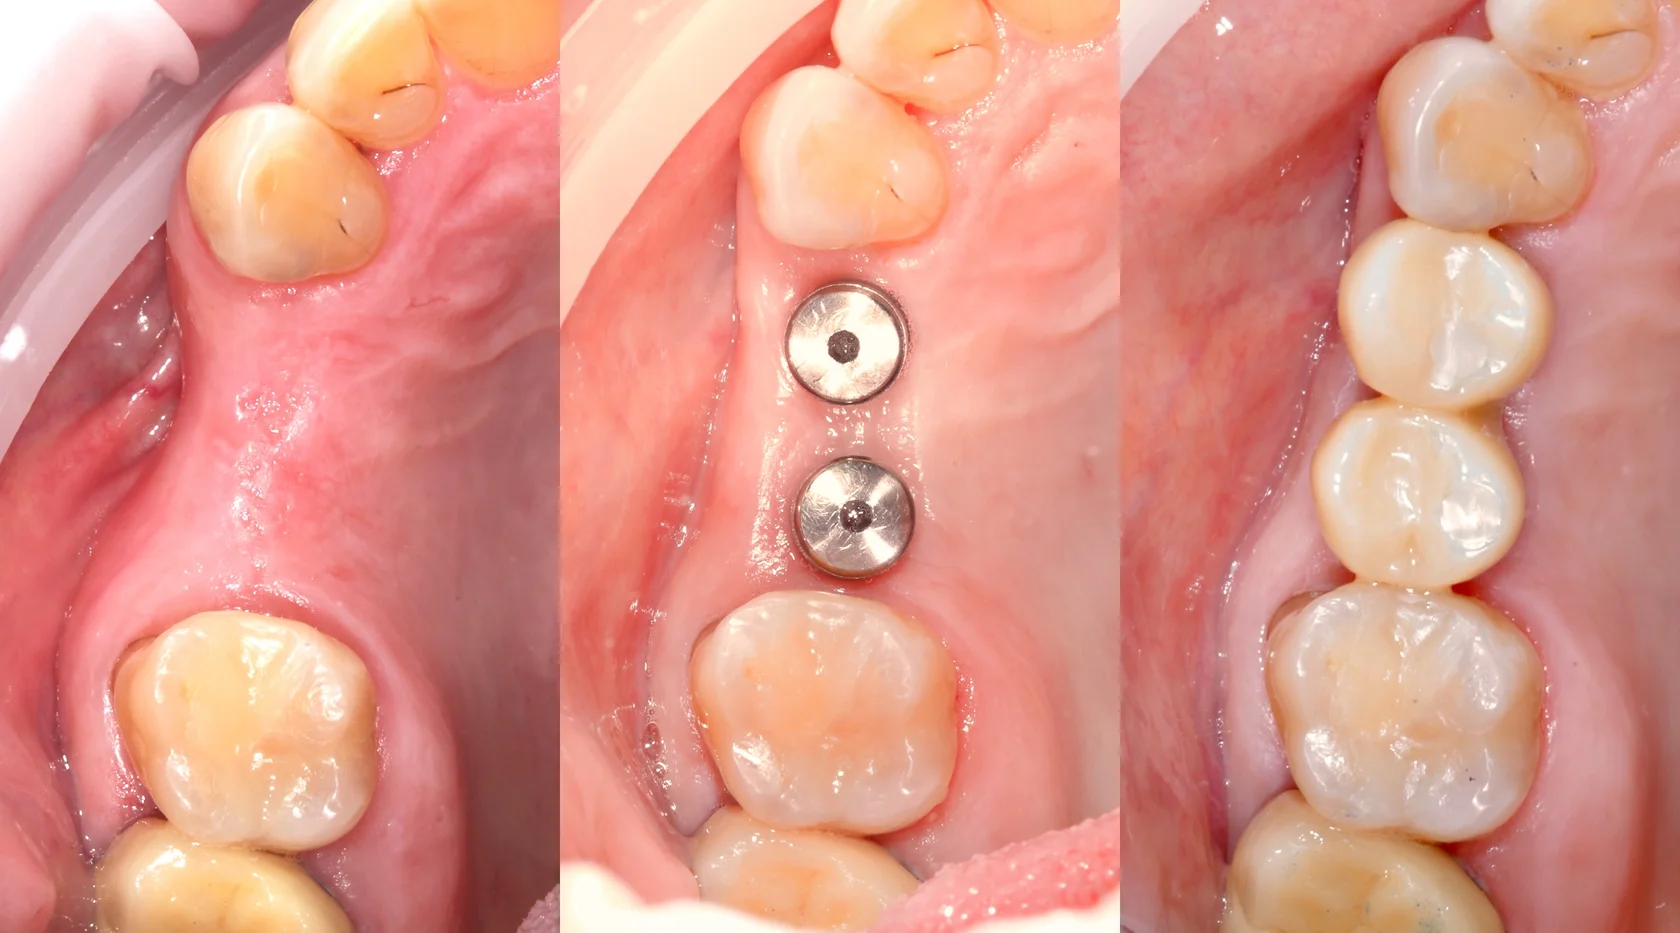

Восстановление одного или нескольких зубов с опорой на имплантаты, когда важно вернуть надёжность, комфорт и естественный внешний вид.

Коронки, виниры, вкладки и другие ортопедические решения в тех случаях, когда зубы ещё можно сохранить и эстетично восстановить.